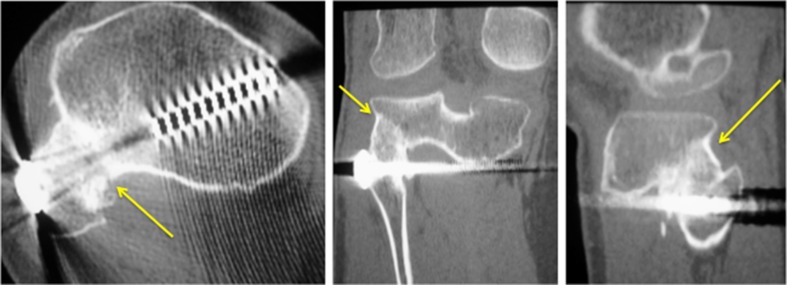

Fig. 4.

(Left to right) axial, coronal, and sagittal CT images, respectively, of the patient in Case 1 demonstrating successful bony fusion of proximal tibiofibular joint (arrows point to the fusion site)